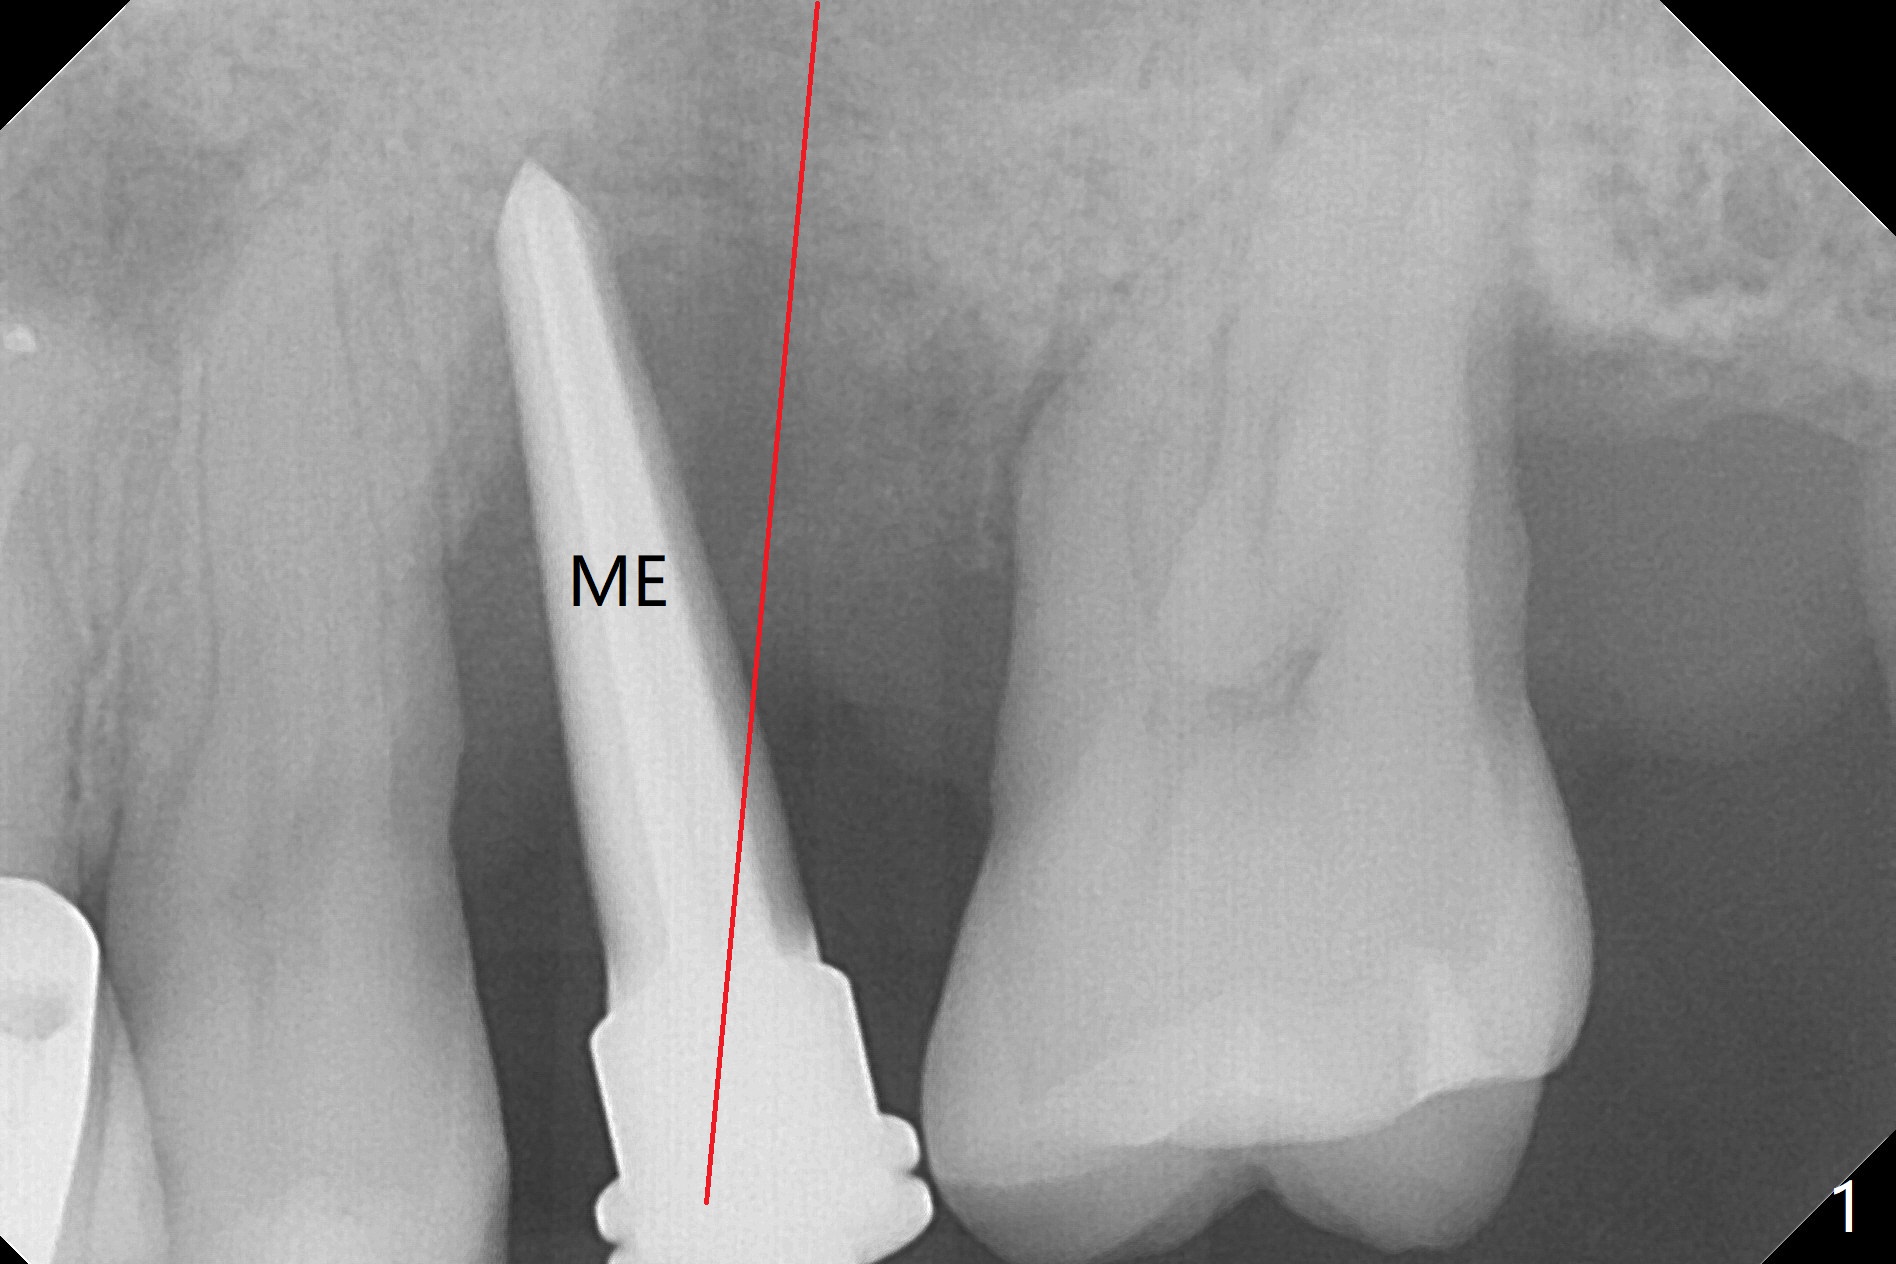

Osteotomy is initiated with Magic Split and 3 mm Magic Expander (ME, flapless) nearly 3 months post socket preservation. To improve the trajectory, the ME is redirected (Fig.1 red line). After use of 3.8 mm ME, Vanilla Graft is placed in the buccal and mesial aspects of the osteotomy. Following reuse of 3 and 3.8 mm MEs, a 4x11 mm dummy implant is inserted with stability (Fig.2 (*: allograft)). More of allograft is placed prior to placement of 5x11 mm IBS implant (Fig.3,4 (~30 Ncm)). The latter is placed palatal. Last the allograft is placed palatal. A 5x4(2) mm abutment is placed to hold periodontal dressing in place. When the ridge is narrow, the implant should be small; 4 mm probably the most appropriate in this case. There is a buccal gap 2 weeks postop (i.e., after dislodgement of periodontal dressing, Fig.5). The implant and abutment appear to be loose ~ 1.5 months postop. The pair abutment is changed to a healing one (5x3mm). The implant seems to be osteotointegrated 3.5 months posotp (Fig.6). Because of the mesial shift of the tooth #15 (Fig.6 arrow (6 months post #14 extraction; anterior open bite)), an angled abutment (5x4mm, 15 degree) is used (Fig.7). Limited orthodontic treatment has to be initiated because the mesially shifted #15 has no occlusal contact mesially (Fig.7 *). A provisional is fabricated with light supra-occlusion. A separator is placed between #14 and 15. Once a space is created in a week, acrylic is added to the distal surface of the provisional and the separator is re-used. In fact the implant is found to be unstable 4.5 months postop (Fig.8,9). The palatal (P) plate is thin and incomplete. The provisional is reduced infraocclusal. Two months the implant remains unstable and is removed.